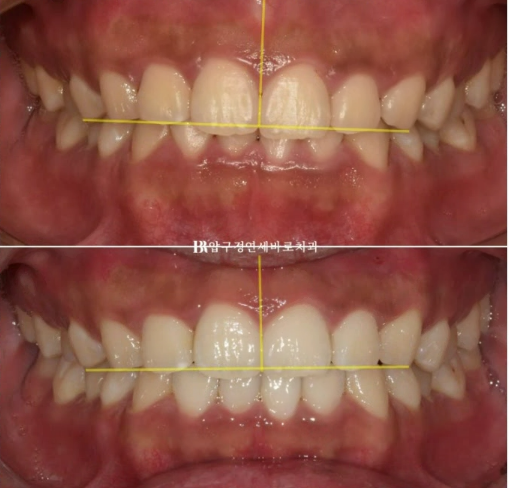

실제로 웃는 사진에서 교합평면이 기울어져 있는 것이 보입니다.

환자분의 왼쪽 치아들이 더 아래로 내려가 있습니다.

웃을 때 이제 더 이상 한쪽 치아가 내려와 보이지 않습니다.

24.02~24.07

기준선을 그으면 교합평면 기울어짐 개선이 더 잘 보입니다.

앞으로는 더 환하게 웃고 사시길 바랍니다.